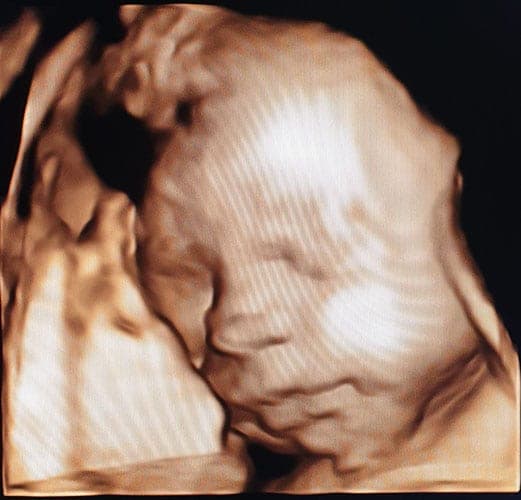

Ultraschallbilder aus dem 3. Trimester (29. bis 40. SSW)

Im dritten Trimester der Schwangerschaft ist das Baby so groß, dass es nicht mehr komplett auf ein Ultraschallbild passt. Nun kann man wunderbare 3D-Ultraschalle des Gesichts machen. In diesem Semester nehmen die Babys nochmal rasant zu und wer Glück hat, kann auf seinem Ultraschall schon erste Gesichtszüge erkennen.

Was genau man auf einem Ultraschallbild erkennen kann, hängt nicht nur von der Größe des Babys ab, sondern auch davon wie gut das Ultraschall-Gerät ist, mit dem die Aufnahme gemacht wurde. Auch auf den Ultraschallbildern hier kannst du sehen, dass die Qualität stark schwankt. In der Regel kann man gut den Kopf und RUmpf des Babys erkennen und auch die Gliedmaßen erkennt man selbst als Laie gut.